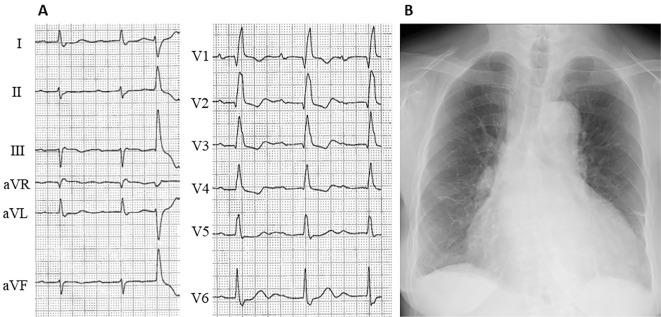

A 72-year-old Japanese woman with systemic sclerosis was admitted to our hospital because of symptoms of heart failure. Cardiovascular magnetic resonance (CMR) imaging had shown that extensive myocardial fibrosis secondary to systemic sclerosis was the main cause of heart failure. One month after CMR, she had complete atrioventricular (AV) block. It was suggested that the progression of fibrosis to the AV node caused complete AV block. This case report has clinical implications in highlighting the fact that CMR is useful for not only evaluating the present pathophysiology but also predicting future adverse events in patients with systemic sclerosis.

一位 72 岁的日本系统性硬化症女性患者因心力衰竭症状被收入我院。心血管磁共振(CMR)成像显示,广泛的心肌纤维化是心力衰竭的主要原因。CMR 后 1 个月,患者出现完全性房室(AV)阻滞。提示纤维化向 AV 结进展导致完全性 AV 阻滞。该病例报告具有临床意义,突出了 CMR 不仅可用于评估当前病理生理学,还可预测系统性硬化症患者未来不良事件的发生这一事实。